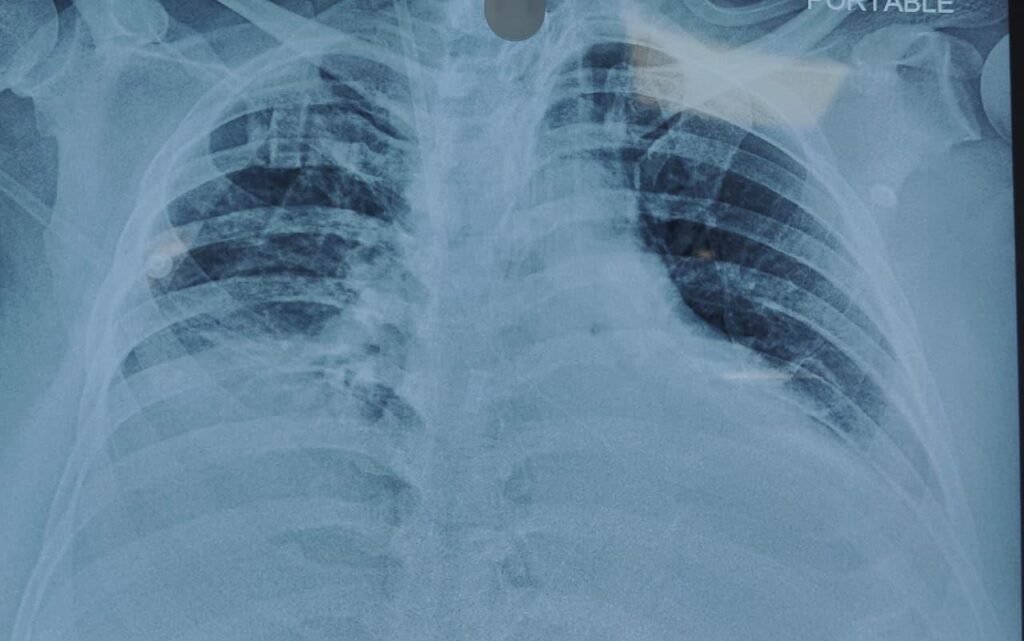

08) Imaging

- Chest X-ray: Bilateral diffuse infiltrates — ARDS pattern